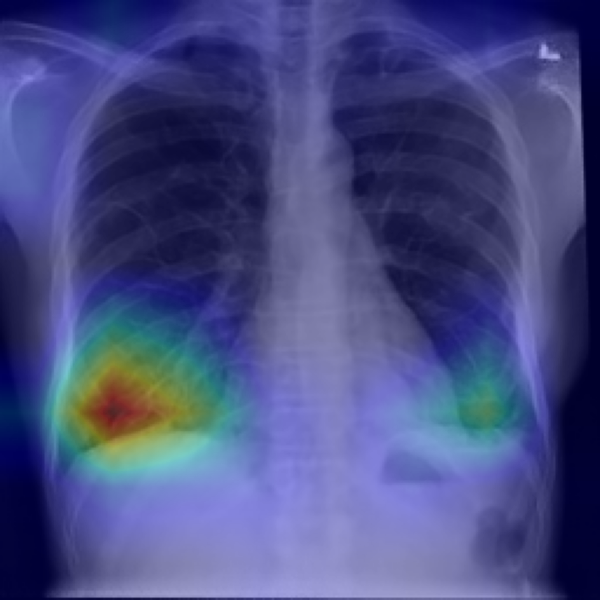

4.2.4 Grad-CAM heat activation map

Figures 33 and 34 show the two end-points ( and ) for one representative X-ray. The CNN‐based neutralizer leaves the hotspots largely intact and increases the male probability from to . In contrast, the ViT neutraliser erases the right-lung focus and tightens the left-lung patch, pushing the classifier to an almost certain male prediction (). Figure 35 presents the full -sweep for the ViT-based neutralizer, confirming that the highlighted sex evidence fades smoothly and the model’s male probability falls toward 0.5 once .